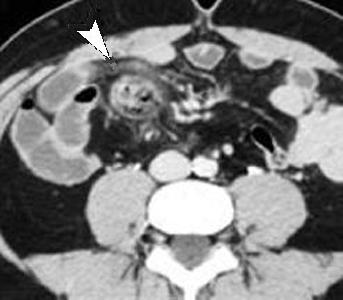

Diverticule de Meckel ( fleche noire ) :

Diagnostic est facile par sa relation de ligament

omphalo mesenterique avec la paroi de l'abdomen a

l'ombilique ( fleche blanche ) |